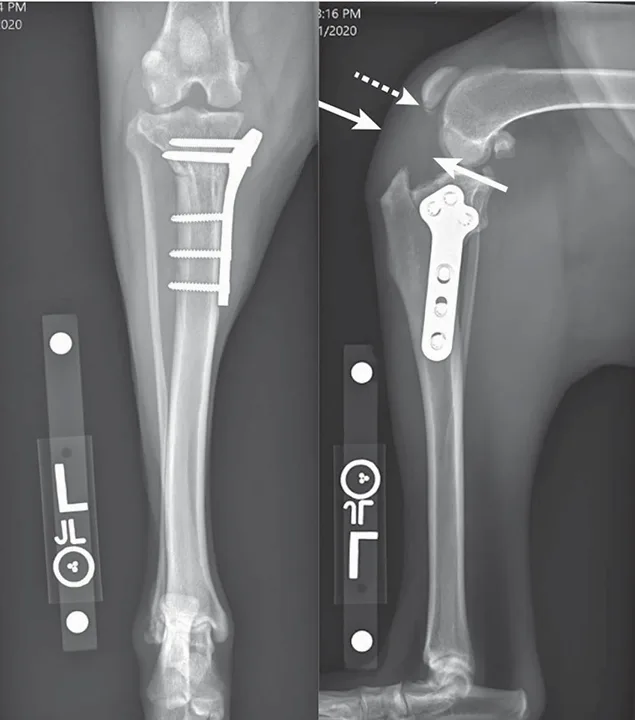

Figure 2

Radiographs from an 8-year-old spayed Rottweiler that underwent TPLO and was diagnosed with a superficial SSI 2 weeks postoperatively at another hospital. The SSI was treated with a 10-day course of antibiotics. The dog was presented to The Ohio State University Veterinary Hospital 6 weeks after surgery for recurrent lameness; the incision was healed, but osteomyelitis was confirmed on radiographs and fine-needle aspirate and cytology. Culture-based antibiotics were prescribed, but the infection did not resolve, the lameness was persistent, and the osteotomy became a nonunion. The patient was euthanized after developing a T3-L3 myelopathy suspected to be related to systemic infection.